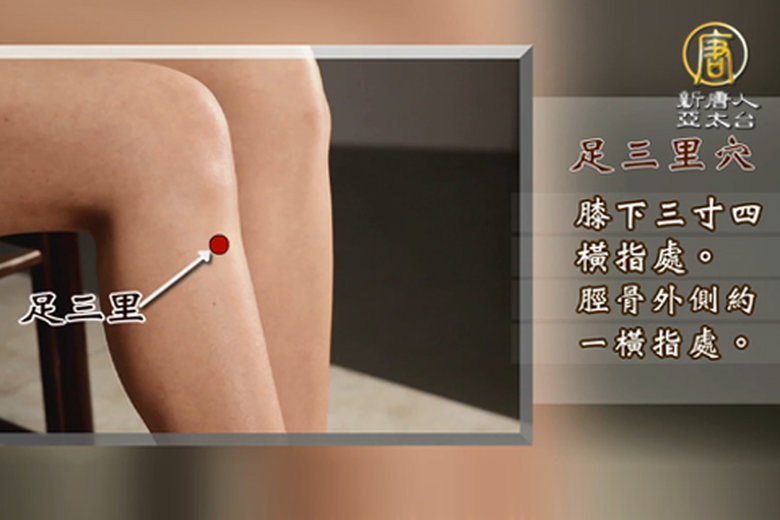

第二單元 胃酸胃痛 按按穴位好輕鬆

中醫除了針灸之外最方便的就是教大家平時按穴位,知道自己的身體哪裡有問題就按哪,沒想到呼吸也是按摩的一種方式,除了足三里啊、內關穴啊、吐納呼吸法是一種內臟按摩耶!不要再亂吃成藥啦~調理好自己的呼吸節奏也能很輕鬆